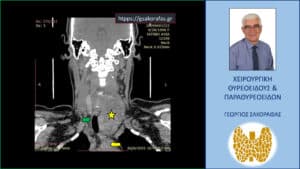

Ευμεγέθης όζος θυρεοειδούς. Αξονική τομογραφία – διατομή σε κατά μέτωπο επίπεδο (διαφορετικό από το προηγούμενο). Ο όζος (κίτρινος αστερίσκος) καταδύεται στο μεσοθωράκιο σε βάθος, φθάνοντας στις παρυφές του αορτικού τόξου (κίτρινο βέλος) και απωθεί προς τα δεξιά την τραχεία (πράσινο βέλος).